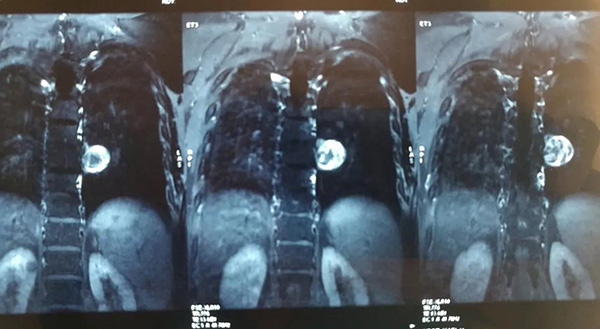

近期,家住齐齐哈尔市龙沙区的张先生因行走无力,来到附近医院就诊,其胸椎核磁共振提示,胸腔内长了一个巨大肿物且侵袭了胸椎管及胸腔,因手术难度大,技术要求高,术中稍有不慎将导致患者瘫痪、胸膜破裂或大血管损伤破裂,甚至死亡,多家医院便都拒绝了张先生的手术需求。因症状一直得不到缓解,辗转多家医院无果,张先生一度陷入了深深的痛苦之中。医生建议他去北京的大医院走走看看,如果前往北京治疗,除了面临高额的手术费用,还要考虑到疫情期间是否可以如期挂号、就诊,难度可想而知。一个偶然的机会,张先生得知齐齐哈尔市第一医院骨外二科主任罗先国在骨科疑难病例的诊治方面颇有建树,于是便在家人的陪同下找到罗先国。

认真阅片并详细查体后,罗先国告知张先生:不用担心,这个手术我们有信心,可以成功完成。面对患者对生命的渴求,罗先国带领团队进行了充分的术前准备,精心制定了手术方案。在相关科室的紧密配合下,为其顺利实施了手术,整个术程十分顺利,巨大肿物被完整切除,神经、胸膜、大血管均完好无缺。术后,患者便可自行下地行走,恢复速度令人称奇。